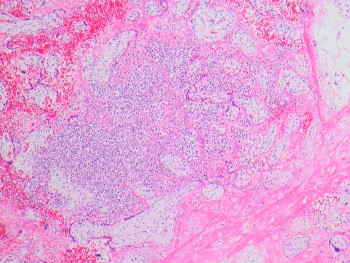

Case History:

A 64 year-old man with history of clear cell renal cell carcinoma s/p nephrectomy (2021) presents with scrotal pain and firmness. Ultrasound reveals a 2 cm solid lesion. Serum tumor markers (hCG and AFP) were normal. The tumor was negative for SALL4, OCT3/4, AFP, and showed focal patchy positivity for pancytokeratin (focal). PAX8 was weakly positive. Additional stains are displayed in the pictures.